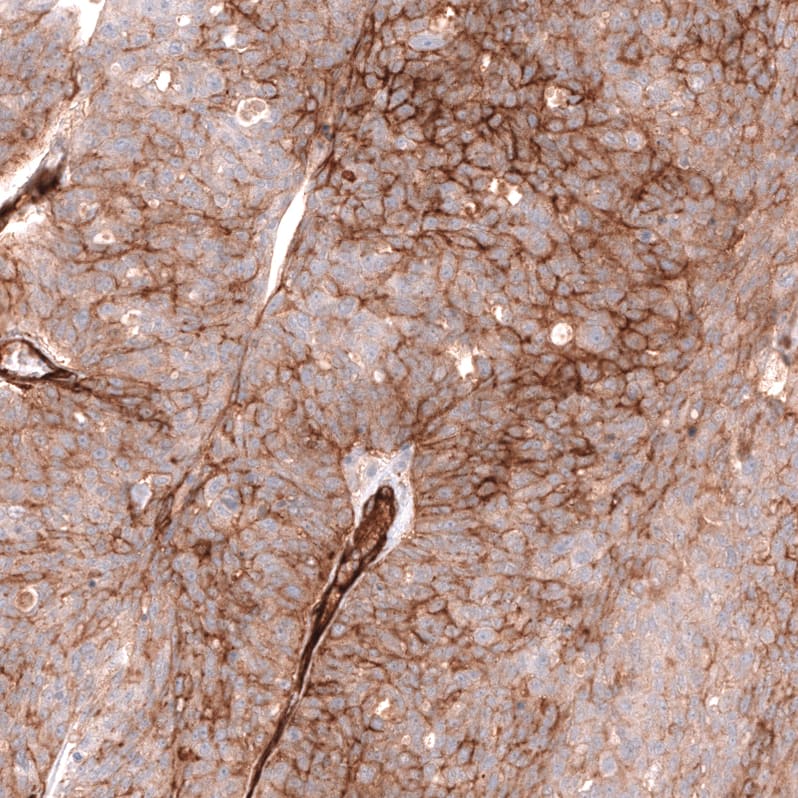

Staining of human ovarian cancer (high grade serous carcinoma) shows moderate to strong membranous positivity in tumor cells.